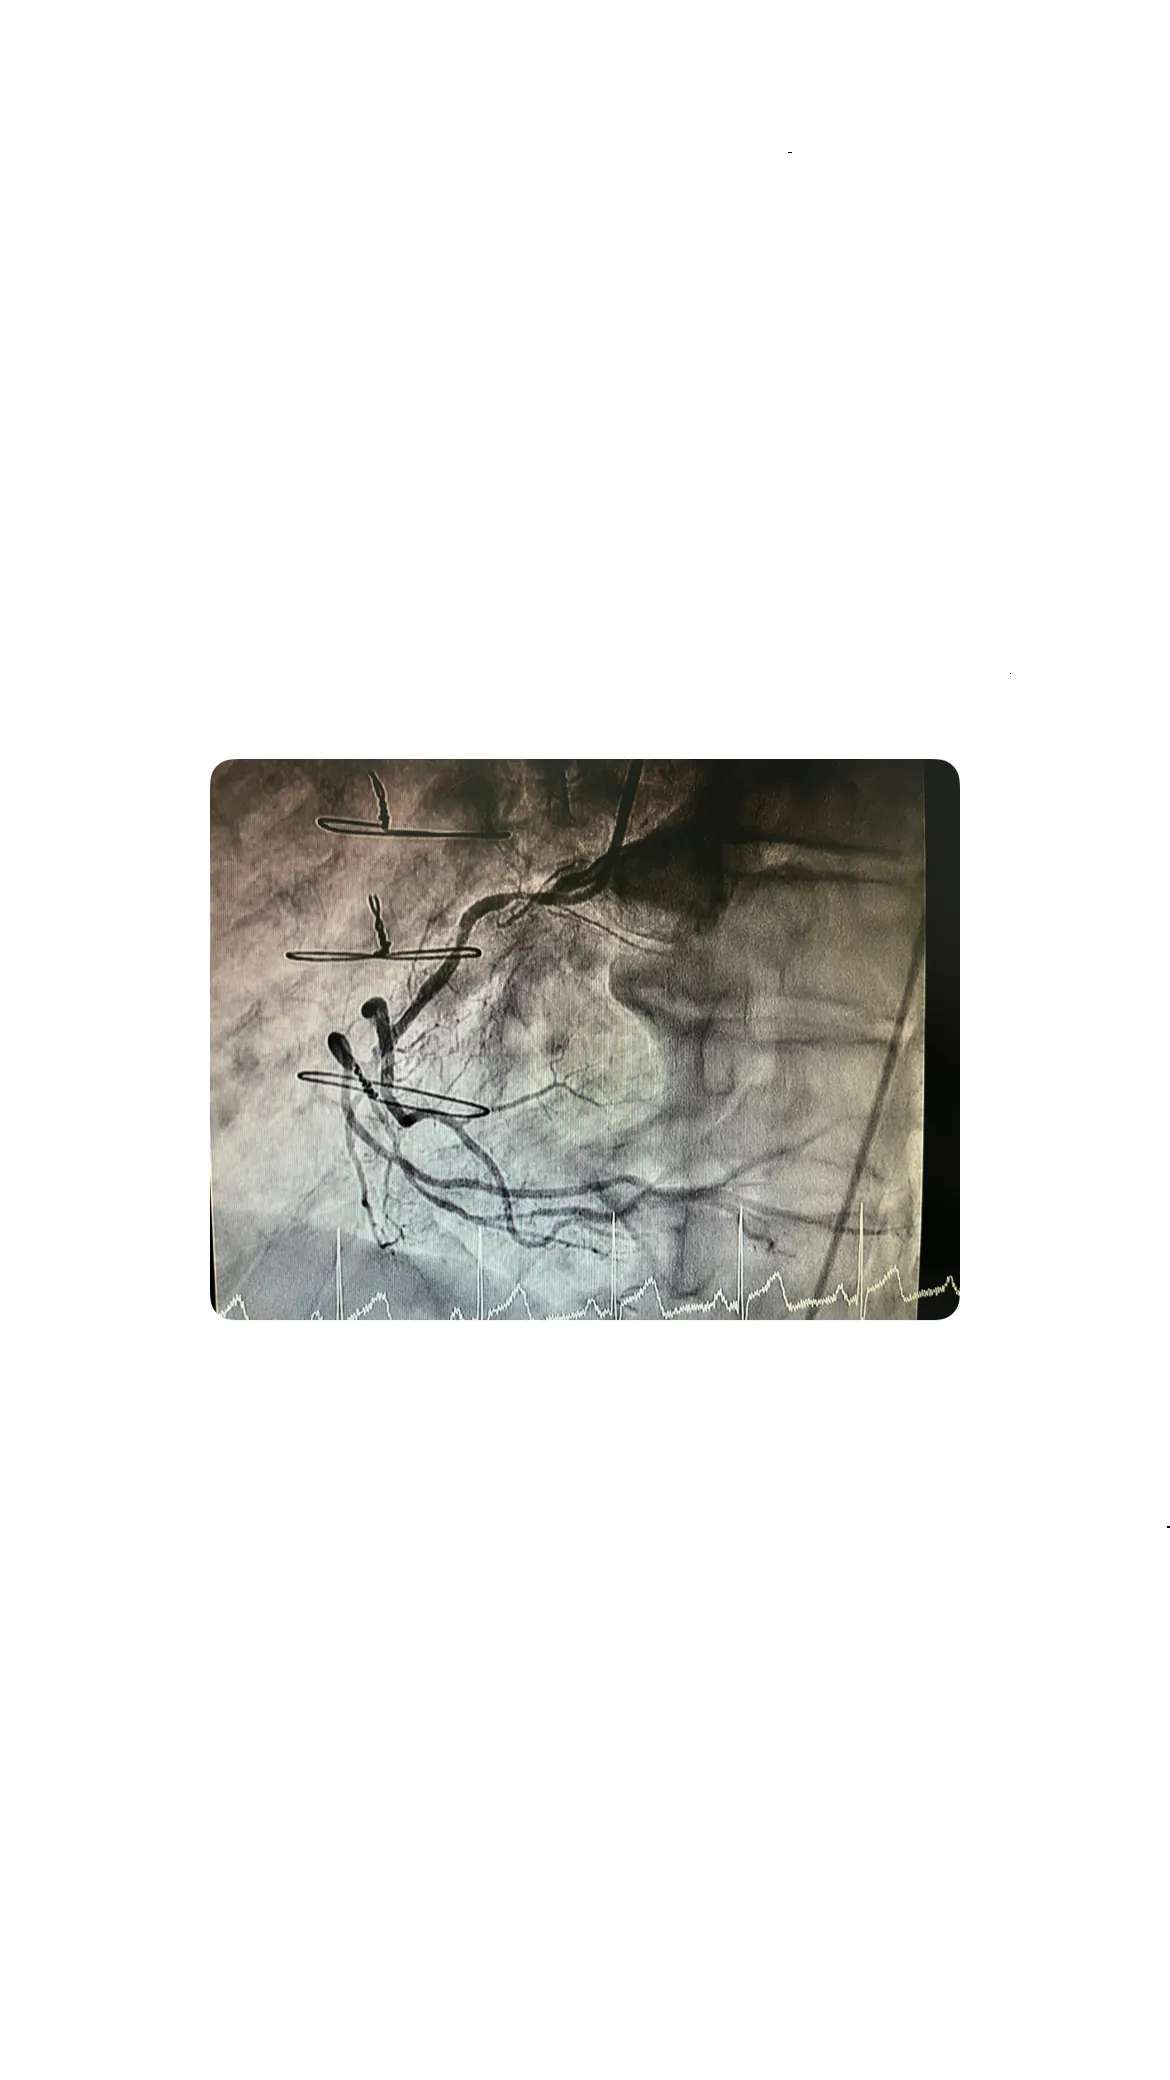

Hallazgos en el árbol coronario izquierdo y el tronco común

Lesión crítica en el tronco común

Durante la evaluación del árbol coronario izquierdo, se identificó una lesión crítica en el tronco común. Este hallazgo es significativo, ya que el tronco común es una arteria principal que suministra sangre a gran parte del corazón. Sin embargo, a pesar de la gravedad de la lesión, los bypasses estaban funcionando adecuadamente, proporcionando un flujo sanguíneo suficiente para compensar la obstrucción.

Relevancia de la permeabilidad de los bypasses

Distribución típica de los bypasses: mamaria y safena

En este caso, los bypasses seguían la distribución típica: la arteria mamaria se utilizó para la arteria descendente anterior (DEA), mientras que las venas safenas se emplearon para la coronaria derecha. Esta distribución es común en las cirugías de bypass y se elige por su eficacia en mejorar el flujo sanguíneo al corazón.

Imágenes angiográficas: grapas, suturas y complejidad del bypass

Visualización de las grapas y la sutura de esternotomía

Las imágenes angiográficas obtenidas durante el cateterismo revelaron detalles interesantes sobre la cirugía de bypass previa. Se pudieron observar claramente las grapas utilizadas en los bypasses y la sutura de la esternotomía. Estos elementos son testimonio de la complejidad y precisión requeridas en este tipo de procedimientos quirúrgicos.

Complejidad anatómica de los bypasses coronarios

La anatomía de los bypasses coronarios es intrínsecamente compleja. Cada bypass debe ser cuidadosamente colocado para asegurar un flujo sanguíneo adecuado y evitar complicaciones. En este caso, la complejidad anatómica fue evidente en las imágenes, destacando la habilidad y precisión del equipo quirúrgico que realizó la cirugía.